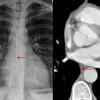

Anterior junction line